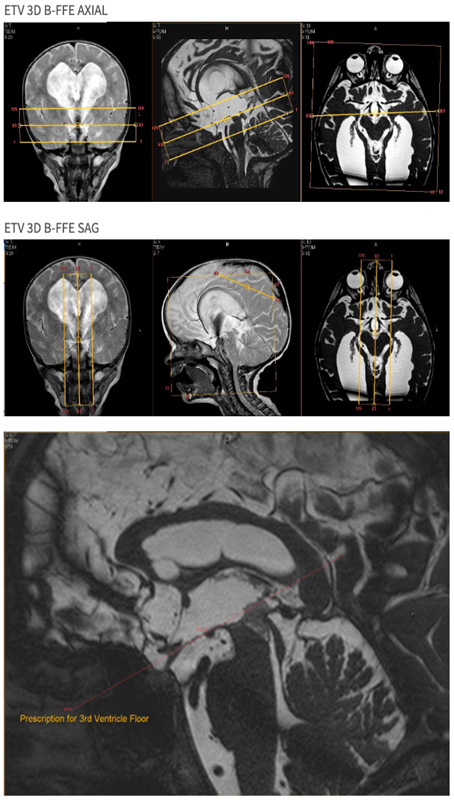

| SAG | 3D Balanced FFE | B-FFE | .58mm | 0mm | None | 16cm | MSP- Centered on 3rd Ventricle |

| OBL AXIAL | 3D Balanced FFE | B-FFE | .58mm | 0mm | None | 16cm | Oblique Angle to Floor of 3rd Ventricle |